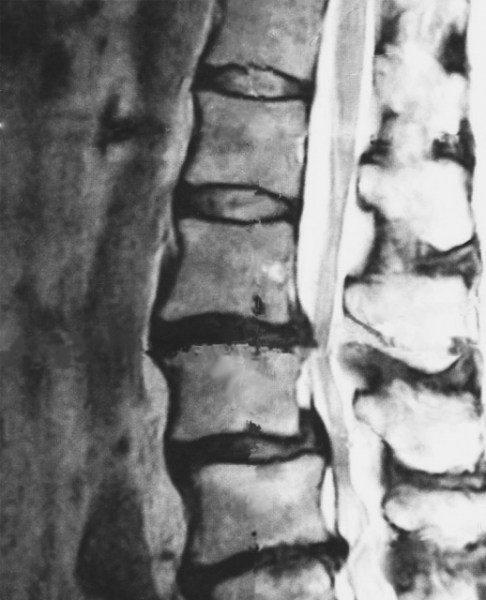

診断結果は、ヘルニアを起こしていた部分の椎間板の画像でしたから、黒くなっているところが椎間板の組織が流れ出て脊椎の神経を圧迫している部分だということで、そのため、少しでも姿勢の角度が変わると神経痛や麻痺症状が出ていたのは、ここが神経を圧迫していたからだということが判ります。

すでに当たっているので、腰を曲げることで神経を更に圧迫してしまっていたのです。

後遺障害の認定ともなると、ムチ打ちや腰痛は日常生活でもなりやすく痛みを訴える人が何万人ともいますのでなかなか認定が下りないと聞いていました。しかし、痛いものは痛いので、MRI画像にも鮮明に映る他覚症状があるということで意地でも保険会社に後遺障害補償を求めることにしたのです。